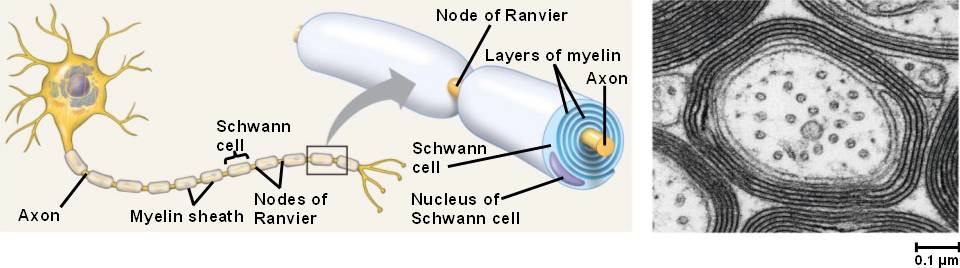

Oligodendrocytes

- Insulate axons in CNS by wrapping in myelin sheaths. Myelination is essential for electrical signal propagation

- Each cell can myelinate multiple axons

Schwann cells

- Myelinate axons in peripheral nervous system (PNS)

- One axon per cell